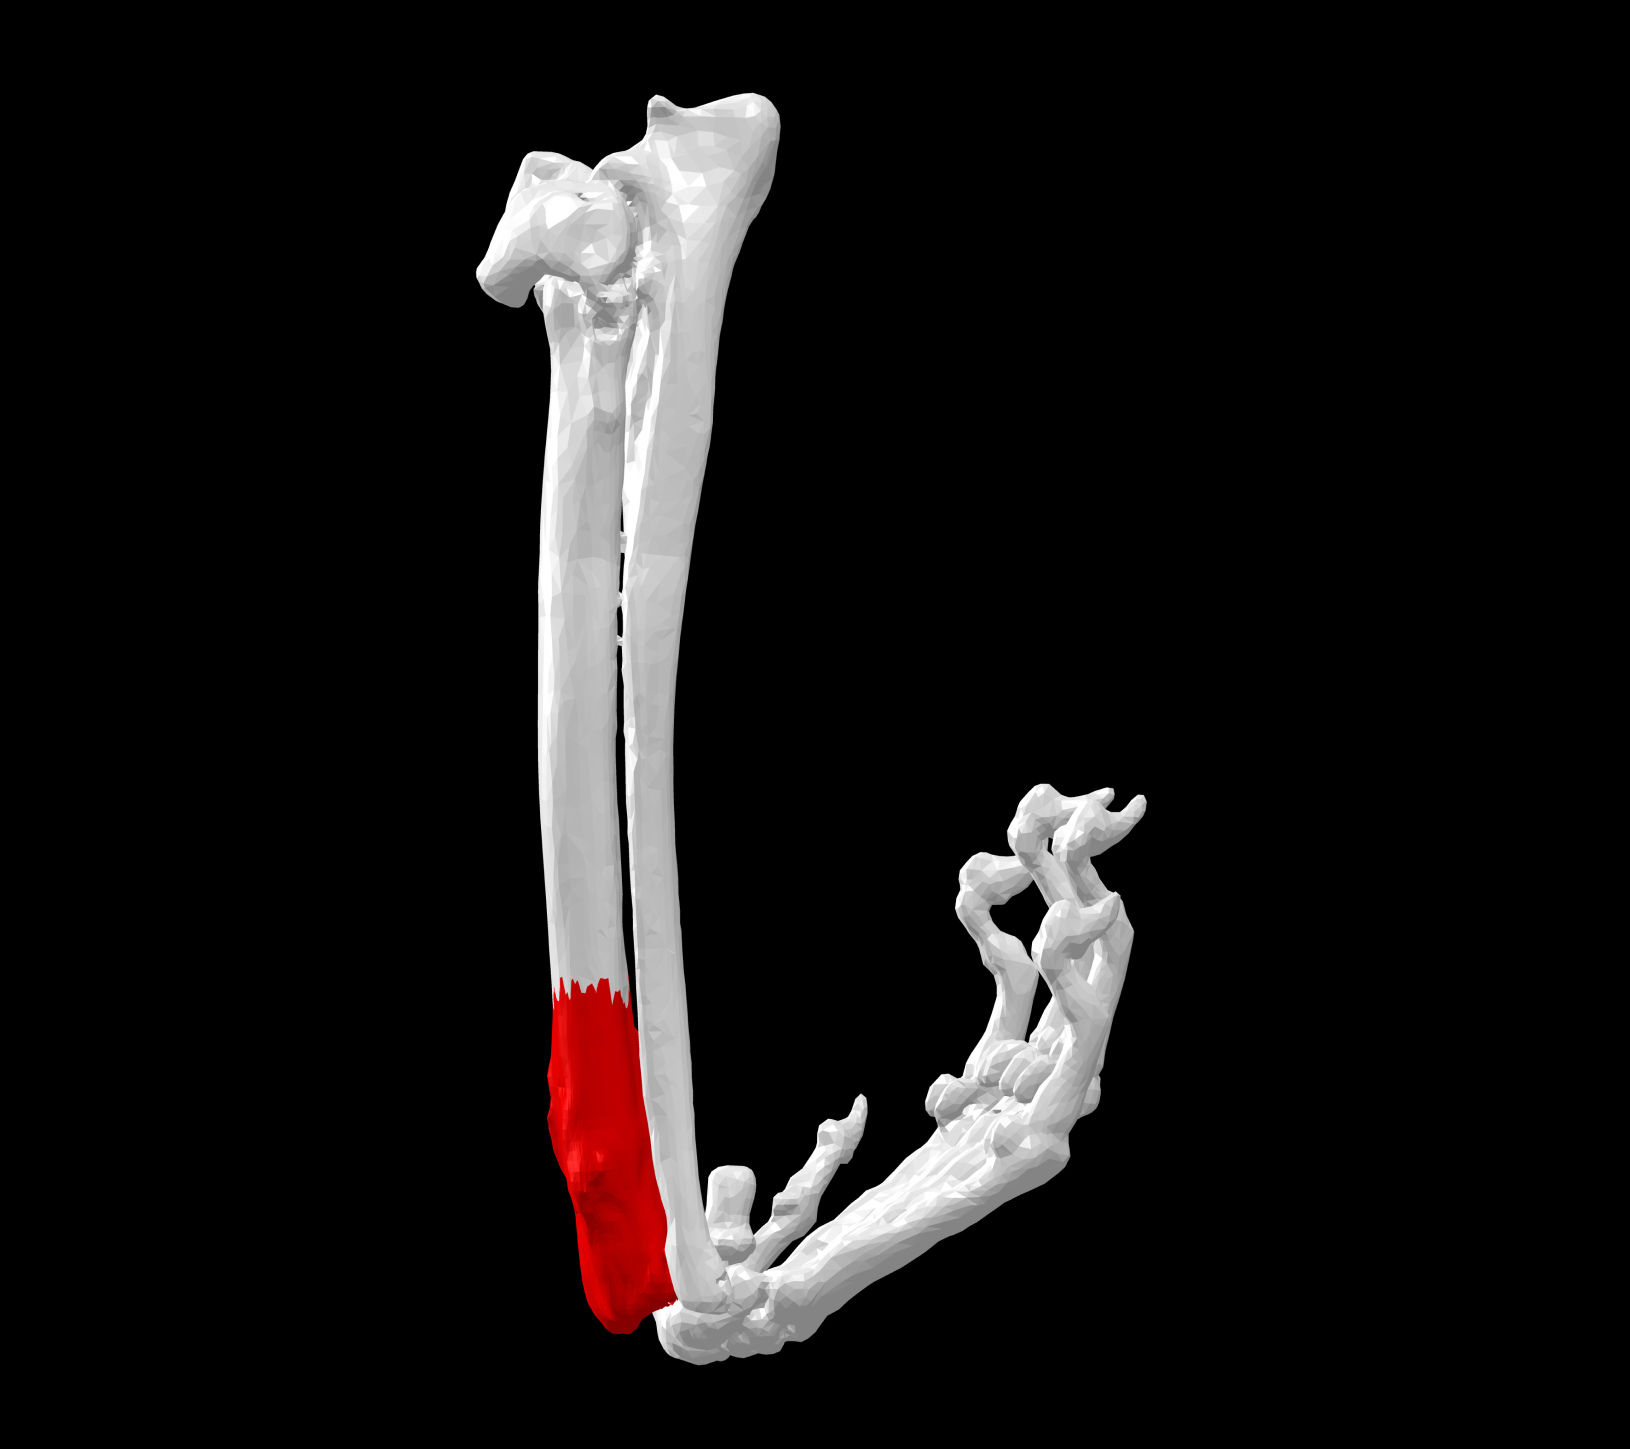

Su aplicación principal es en pacientes con neoplasias (tumores) óseas, como es en la mayoría de casos el osteosarcoma. Ante esta situación tradicionalmente era necesario llevar a cabo una amputación radical del miembro afectado. Actualmente gracias a técnicas de salvación de miembro, siempre y cuando el estado de salud general del paciente lo permita, es posible la resección quirúrgica del tumor y la reconstrucción de la extremidad afectada empleando diferentes prótesis anatómicas que ayudarán a restaurar la estructura y la función del miembro afectado.